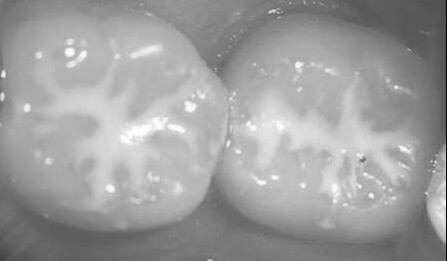

Ez a kezelés egy megelőző céllal segíti a gyermekek rágófogainak mély barázdáinak védelmét.

Gyermekeknél a fogszuvasodások 60-80%-a a rágófelszíni barázdákban és gödröcskékben kezdődik, ezek képezik a fogak legsérülékenyebb területeit. A barázdazárás éppen ezekre a veszélyeztetett területekre jelent foganyag kímélő hatékony megelőzési technikát.